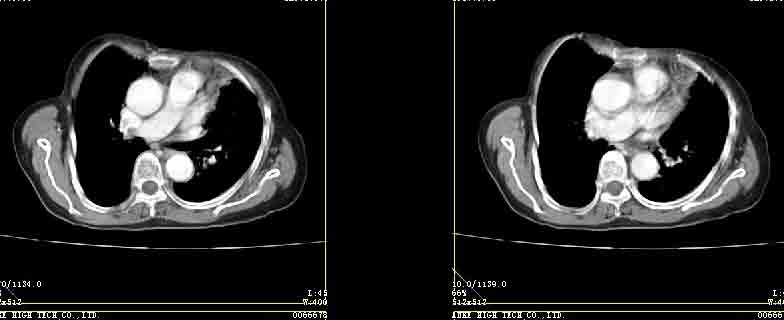

女77岁因左侧胸痛伴咳嗽入院;提示:病灶平扫45hu,强化145hu补充:双肺内未闻及干湿罗音

定位肺内,强化显著(100hu以上),考虑感染性病变先,抗炎后复查排除占位。

我的诊断意见:左肺上叶前段肺癌伴节段性不张。

在不张的肺内见到不规则的软组织,而且强化是不均匀的(该点可能是我的图像作得不好的原因)。

强化密度略高于肌肉 考虑周围型肺癌【小箭头为容积效应现象】

左上肺前段可见分叶团块影,强化明显,周围见带状不张影,右肺结节,左肺沿肺纹模糊片状影,考虑左上肺占位,肺癌可能性大。